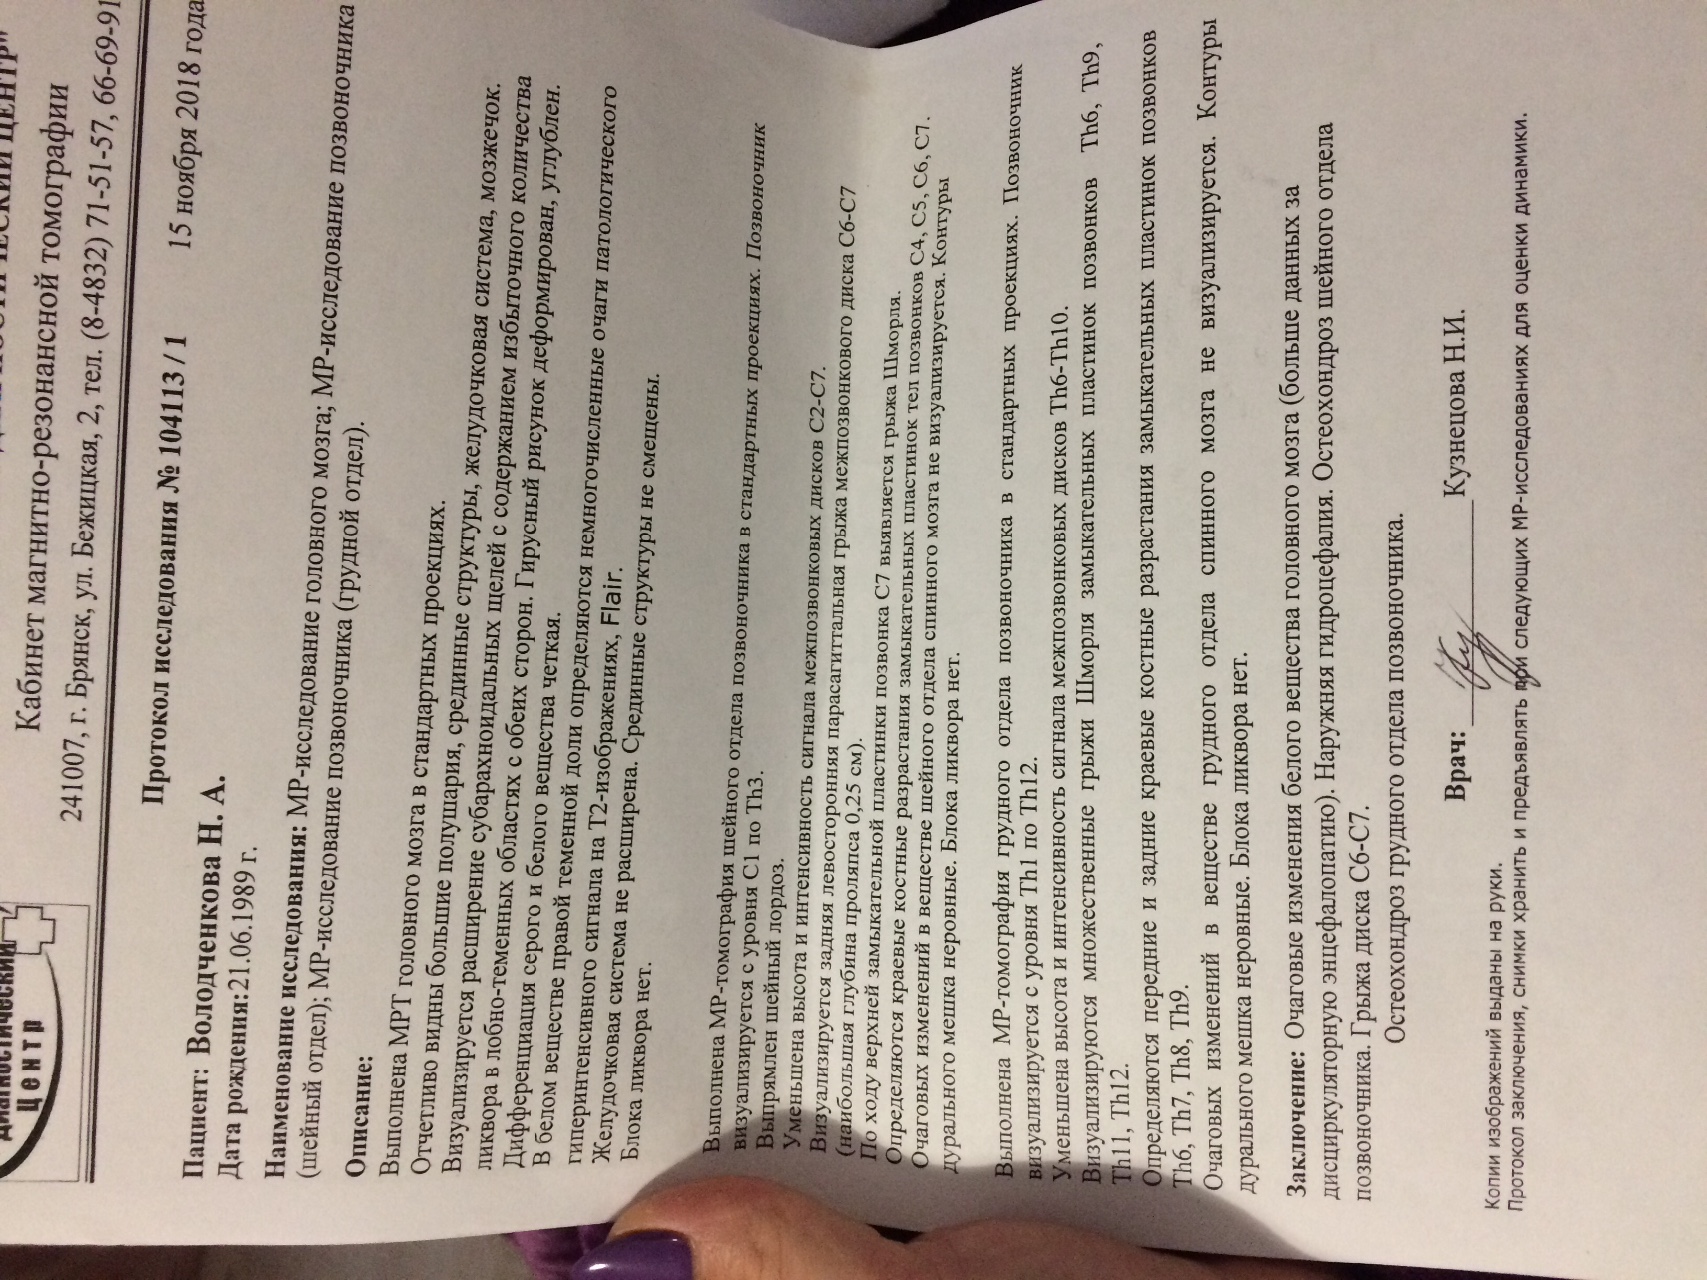

Демиелинизирующие заболевания мозга: МРТ изображения

Раздел: Путеводитель по жизни